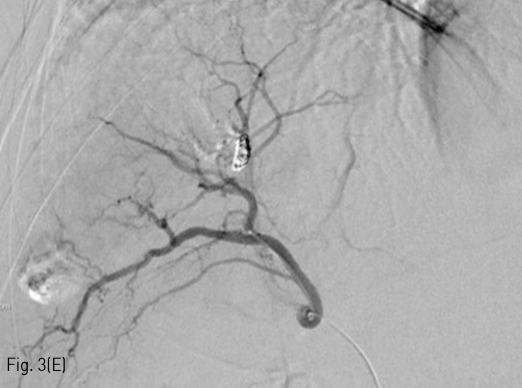

Fig 3E

(E) Post-embolization arteriography showed complete occlusion of arterioportal shunt.

5Fr RH catheter (Cook, IN, USA)를 이용하여 총간동맥을 선택한 후 시행한 선택적 조영술에서 우측 후방 간문맥이 조영되면서 7번 간분절 동맥과 문맥 사이의 대량의 간동문맥단락 소견이 있었다(Fig. 3A, 3B). 1.9Fr microcatheter (Radiostar, Taewoong, Gyeonggi-do, Korea) 를 이용하여 간동문맥단락의 원인이 되는 혈관을 superselection 한 후, Interlock detachable coil (Boston scientific, MA, USA) 2mmx6cm과 K3 pushable coil (Taewoong, Gyeonggi-do, Korea) 2mmx2cm, 2mmx5cm을 이용하여 코일 색전술을 시행하였다 (Fig. 3C). 추가로 N-butyl-2-cyanoacrylate (histoacryl; B.Braun)와 Lipiodol (Guerbet) 1:3 혼합물 0.5mL을 이용하여 색전술을 시행하였다 (Fig. 3D). 색전술 후 시행한 간동맥의 선택적 조영술에서 간동문맥단락이 소실됨을 확인하였다(Fig. 3E).